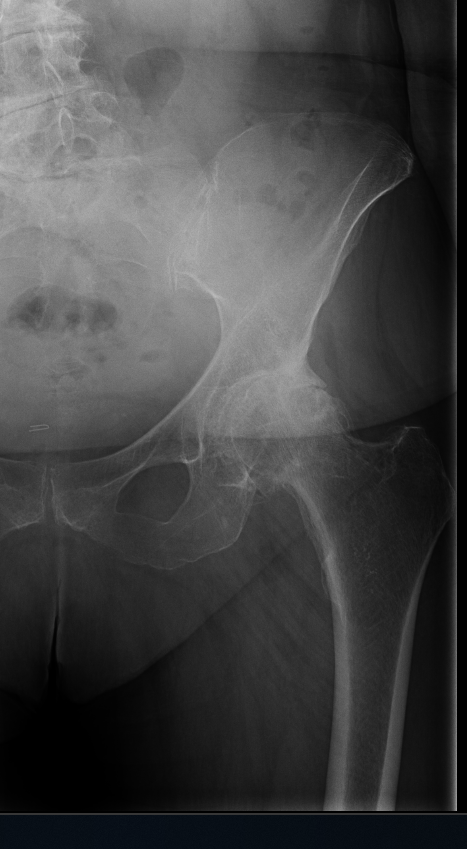

Arthritis is inflammation of the joints resulting in pain, swelling, stiffness and limited movement. Hip arthritis is a common cause of chronic hip pain and disability. The three most common types of arthritis that affect the hip are:

- Osteoarthritis: It is characterized by progressive wearing away of the cartilage of the joint. As the protective cartilage wears down, the bone ends rub against each other and cause pain in the hip. Rheumatoid arthritis: This is an autoimmune disease in which the tissue lining the joint (synovium) becomes inflamed, resulting in the production of excessive joint fluid (synovial fluid). This leads to loss of cartilage causing pain and stiffness.

- Traumatic arthritis: This is a type of arthritis resulting from a hip injury or fracture. Such injuries can damage the cartilage and cause hip pain and stiffness over a period of time.

The most common symptom of hip arthritis is joint pain and stiffness resulting in limited range of motion. Vigorous activity can increase the pain and stiffness which may cause limping while walking.

Diagnosis is made by evaluating medical history, physical examination and X-rays.